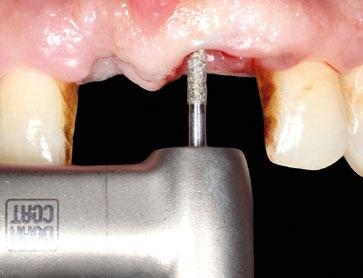

Se comienza con la exodoncia del 2.1 de forma atraumática y el legrado minucioso del alveolo. Para asegurar la correcta remoción de restos epiteliales de la bolsa periodontal se realiza curetaje rotatorio a baja velocidad con fresa de diamante de grano grueso (aro verde). (Figuras 4 y 5). Para llevar a cabo la regeneración ósea guiada se facilita el acceso tunelizado, mediante dos incisiones VISTA modificadas a nivel de la mucosa alveolar de 13 y 23, de las membranas reabsorbibles así como del injerto de tejido conectivo. A nivel de 1.1 se hace una incisión circular sin descargas a modo de ojal supracrestal.

Una vez desbridados los tejidos cicatriciales y de granulación de ambos defectos y habiendo minimizado la tensión de todo el tejido mucoso diseccionando a espesor total y parcial el túnel se procede a colocar ambos implantes en la posición 3D ideal teniendo como referencia la futura posición de los márgenes gingivales de 1.1 y 2.1. Así, la plataforma de ambos Prama se colocan a 1,5 mm apica -